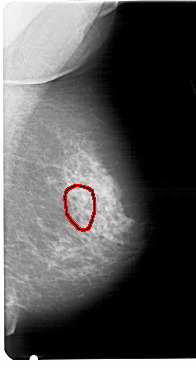

A_1458_1.LEFT_MLO

FILE: A_1458_1.RIGHT_MLO.OVERLAY

TOTAL_ABNORMALITIES 1

ABNORMALITY 1

LESION_TYPE CALCIFICATION TYPE PLEOMORPHIC DISTRIBUTION CLUSTERED

ASSESSMENT 4

SUBTLETY 3

PATHOLOGY BENIGN

TOTAL_OUTLINES 1

BOUNDARY